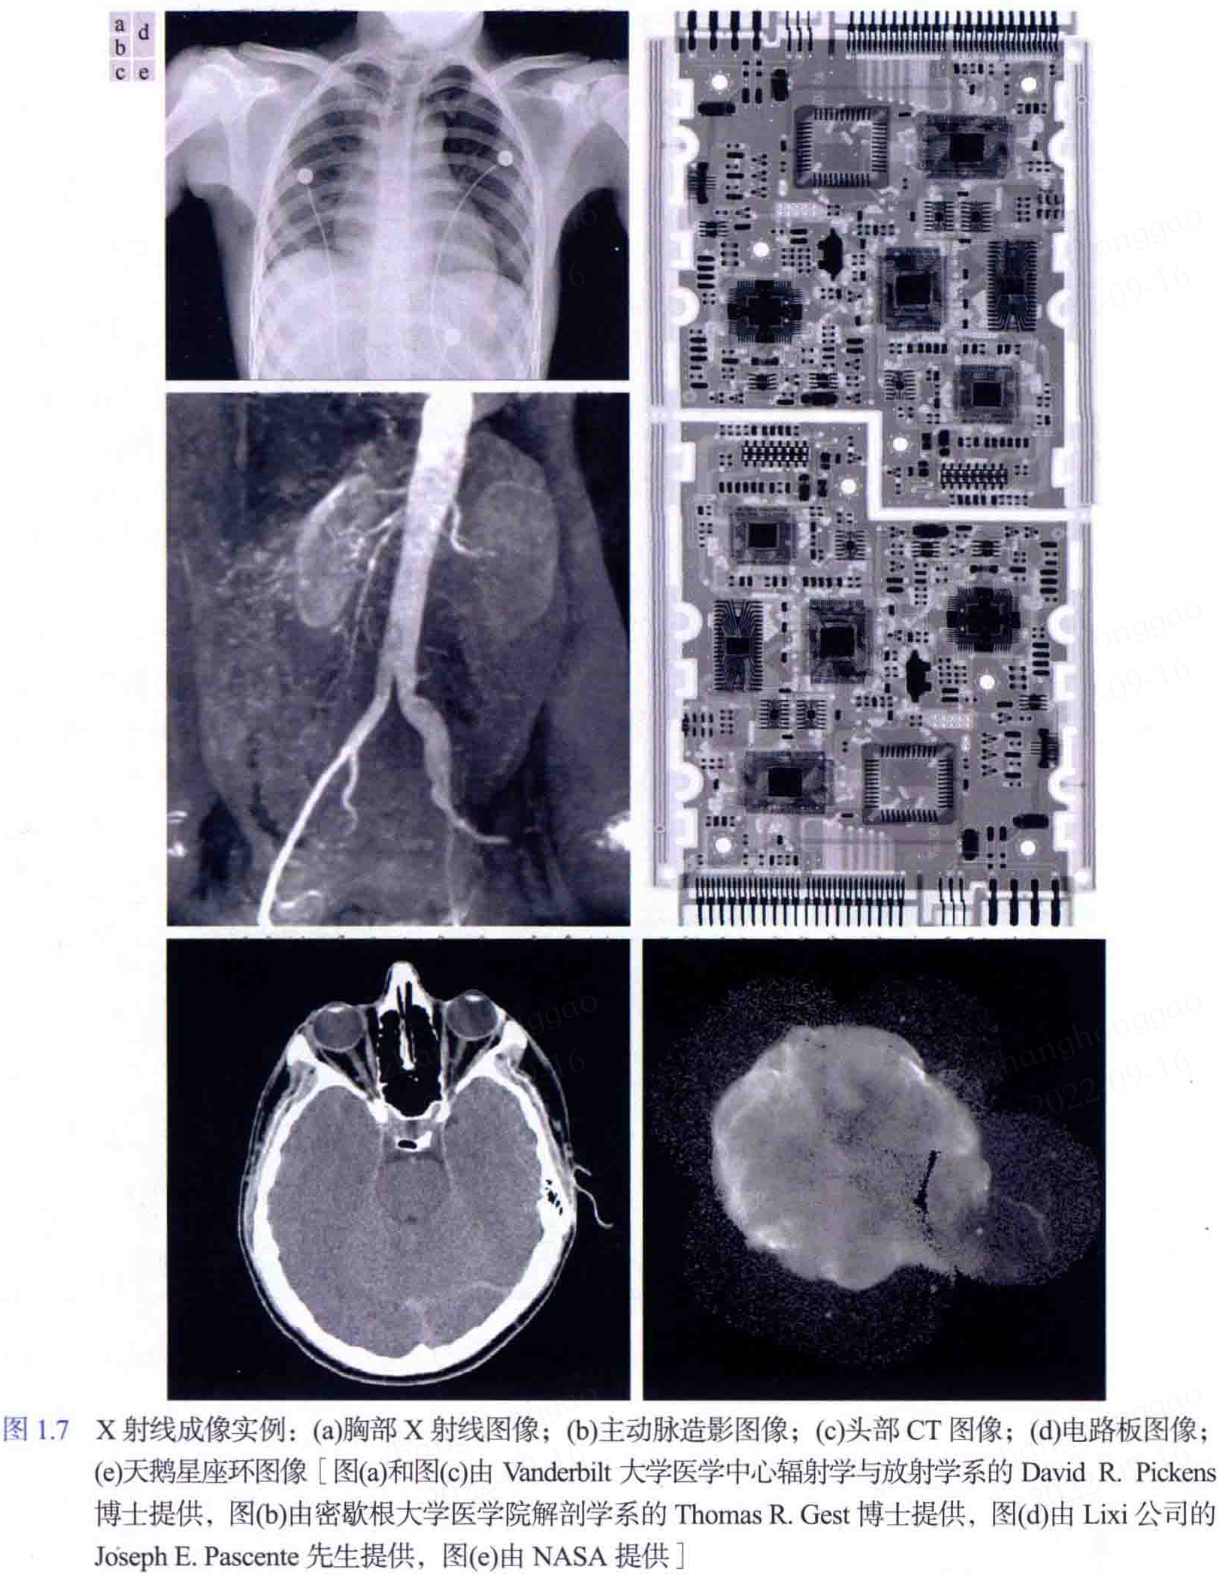

- X 射线成像:X 射线成像除了应用于医学诊断,还被广泛应用于工业和其他领域,如天文学。

一些图像实例效果图如下图所示。